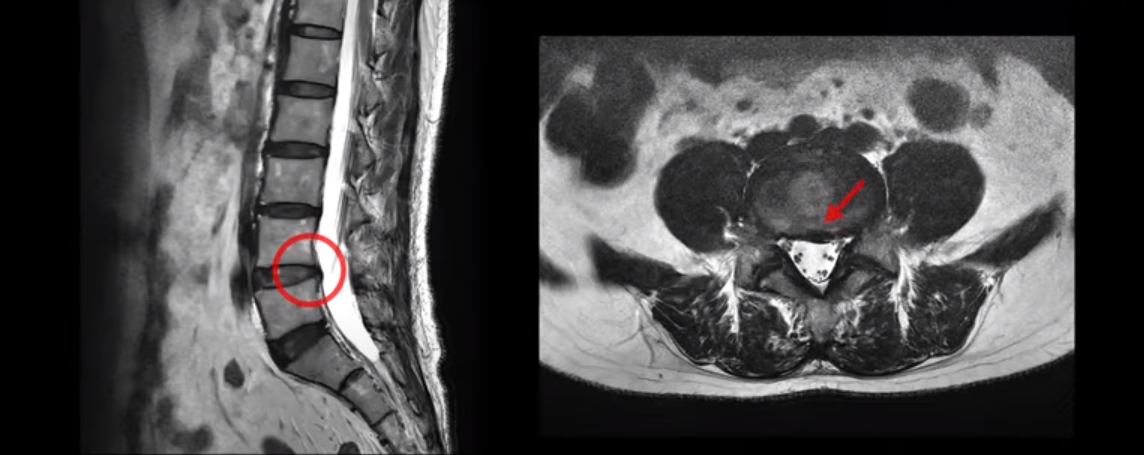

양쪽 다리저림, 24시간 양쪽 발저림, 엉덩이 통증, 좌골신경통 환자의 MRI 상태 및 증상은?

보시다시피 이 환자분의 4, 5번 디스크는 심하지 않습니다.

또한 신경이 나가는 구멍도 넓은 상태로 신경을 누르는 것도 보이지 않습니다.

그런데 이 환자분의 제일 괴로운 증상은 양쪽 발이 저린 증상인데 앉아있어도 저리고 걸어도 저리고 누워도 저린 24시간 다리가 저리는 증상입니다. 또 앉아만 있으면 엉덩이 쪽으로 통증이 심해져서 앉아있기도 힘든 상황이었습니다.

이런 상황에서 정형외과, 신경외과 병원들에서 디스크 증상일 수 있다며 시술과 주사 치료를 여러 차례 받으셨습니다. 그런데 아무 효과가 없었고, 한 마취통증과에서는 디스크가 확실히 아니기 때문에 치료해 줄 게 없다는 말씀을 들으셨고 또 한 정형외과 병원에서는 천장관절에 염증이 있다고 해서 주사 치료를 받았으나 역시 효과가 없었고 또 다른 병원에서는 천장관절에 염증이 없다는 얘기를 들으셨습니다.

그런데 이분처럼 디스크 증상이 아닌데도 MRI에 디스크가 조금이라도 보이니까 허리 치료만 받느라 시간을 보내며 고생하시는 분들이 매우 많습니다. 이분의 하지 증상은 양쪽 발 저림 증상입니다. 보통 한쪽 다리가 아픈 디스크로는 설명될 수 없는 증상입니다. 또한 이 분의 등, 허리, 엉치, 허벅지 근육은 전체적으로 엄청나게 뭉쳐있는 상태였습니다.

이런 상태에서는 등부터 허리와 골반에서 일상생활로부터 생기는 부담이나 충격을 흡수하는 메커니즘이 모두 깨져 있기 때문에 모든 충격과 부담이 다리와 발 쪽으로 쏟아지는 겁니다. 그래서 다리와 발이 저린 겁니다. 증상이 좀 덜 심한 분들은 누우면 증상이 좀 줄어들지만, 이분은 증상이 매우 심한 분으로 누워도 발 저림이 계속 발현되는 상황이었습니다.